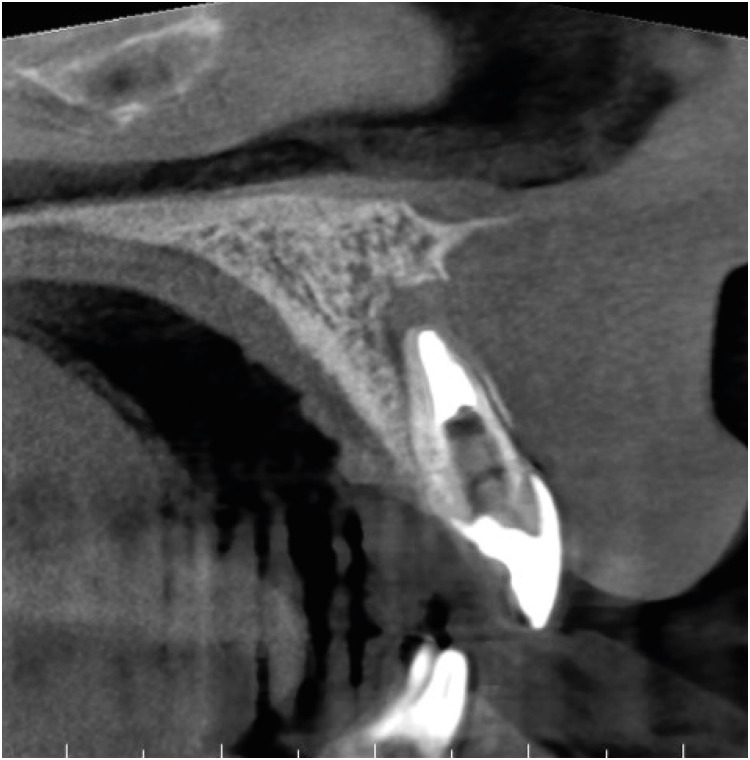

A follow-up CBCT scan was taken 1 year after the final root canal treatment and revealed continued healing of the periapical radiolucency and reformation of the buccal bony wall around the apex (Figure 5). The tooth has remained asymptomatic ever since, and the patient was satisfied with the result.

Figure 5

Follow-up cone-beam computed tomography scan taken 1 year after the finalization of root canal treatment, showing the homogeneity of the short-fiber reinforced composite inside the canal.

This case indicates that the Bioblock technique could be an effective and relatively easy way to restore and likely to reinforce even advanced cases of IRR in the anterior dentition. The case also emphasizes the importance of using CBCT in cases of resorption when periapical X-ray imaging does not provide sufficient information about the extent of the lesion.